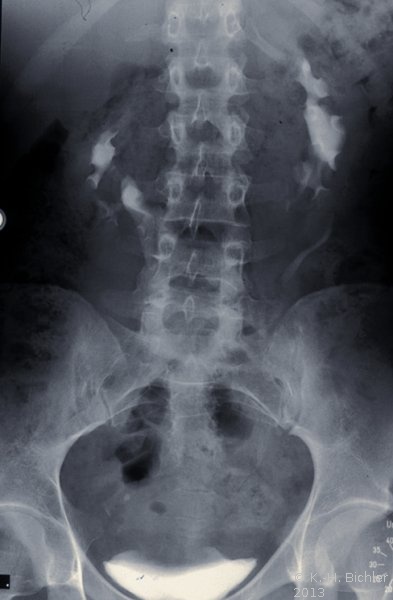

Bei einer jugendlichen Patientin kam es in Folge eines aberrierenden Gefäßes zum Harnstau im linksseitigen Hufeisennierenanteil mit Ausbildung eines fieberhaften Harnwegsinfektes. Unter der Diagnose eines aszendierenden, fieberhaften Harnwegsinfektes wurde die Patientin stationär aufgenommen, nach antibiotischer Therapie, parenteraler Flüssigkeitsapplikation und Bettruhe entfieberte die Patientin. Die Diagnostik ergab in der Sonographie einen Harnstau im linken Nierenanteil mit Verdacht auf Hufeisenniere (Abbildung 4).

Im Ausscheidungsurogramm und im CT war eine Hufeisenniere mit Pyelektasie links zu erkennen (Abbildung 5).